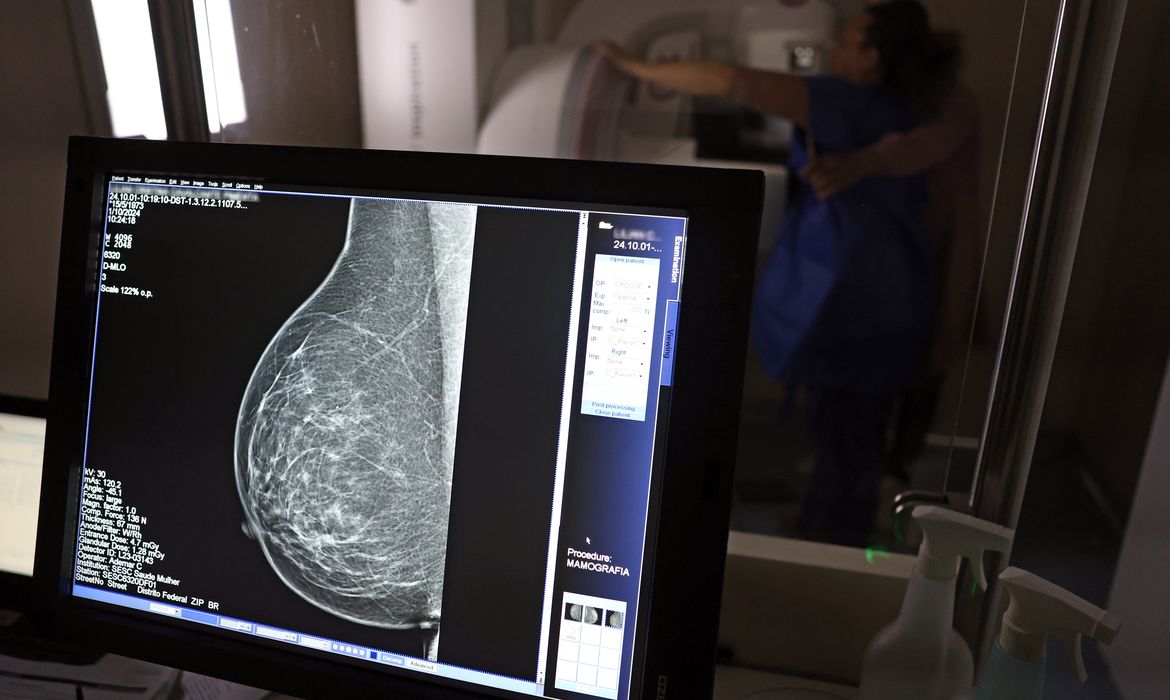

A partir de quantos anos se deve fazer a mamografia de rastreio, ou seja, como um exame de rotina, mesmo sem sintomas? Para autoridades públicas, como o Ministério da Saúde e o Instituto Nacional do Câncer (Inca), o ideal é que a mamografia seja feita a cada dois anos por todas as mulheres entre 50 … Continued

A partir de quantos anos se deve fazer a mamografia de rastreio, ou seja, como um exame de rotina, mesmo sem sintomas? Para autoridades públicas, como o Ministério da Saúde e o Instituto Nacional do Câncer (Inca), o ideal é que a mamografia seja feita a cada dois anos por todas as mulheres entre 50 e 69 anos. Algumas entidades médicas, como a Sociedade Brasileira de Mastologia (SBM), entretanto, recomendam exame anual a partir dos 40 anos.

Roberto Gil explica por que esses estudos consideram que os 50 anos são a idade certa para o início do rastreamento na população em geral: “Não estamos negando que mulheres abaixo de 50 anos tenham câncer de mama. Estamos falando que, abaixo dos 50 anos, acumulam-se outros problemas e o rastreamento populacional é menos eficiente. A mamografia é um exame de raio X, que vai ser mais efetivo na medida que a mama seja menos densa e que se tenha mais contraste na imagem, para não se confundir o parênquima normal com um nódulo. Então [antes dessa idade], aumenta muito mais a possibilidade de ter falsos positivos e ter que fazer mais exames. Posso fazer uma biópsia e ser mais difícil interpretar e levar a uma cirurgia desnecessária.”